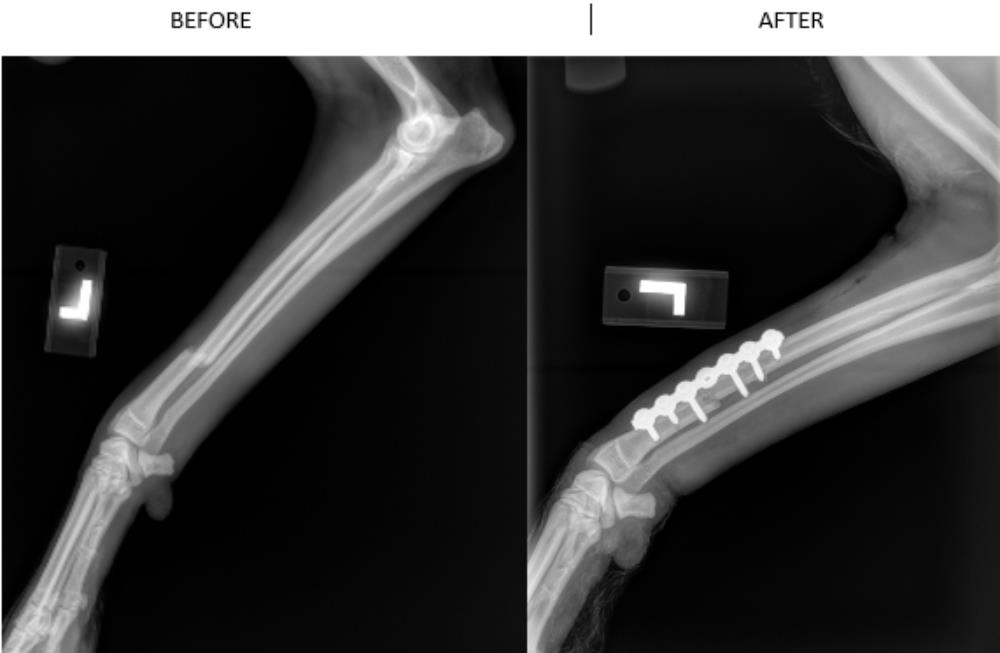

At Western Veterinary Services, we understand the importance of being here when you need us. We will continue to provide the routine cattle services and companion animal care that you have come to expect. In addition to the planned visits, we want to be there if a problem comes up. That’s why we are committed to keeping our specialized equipment, in house bloodwork, x-rays and hospital facilities along with our full line of veterinary products to serve you.